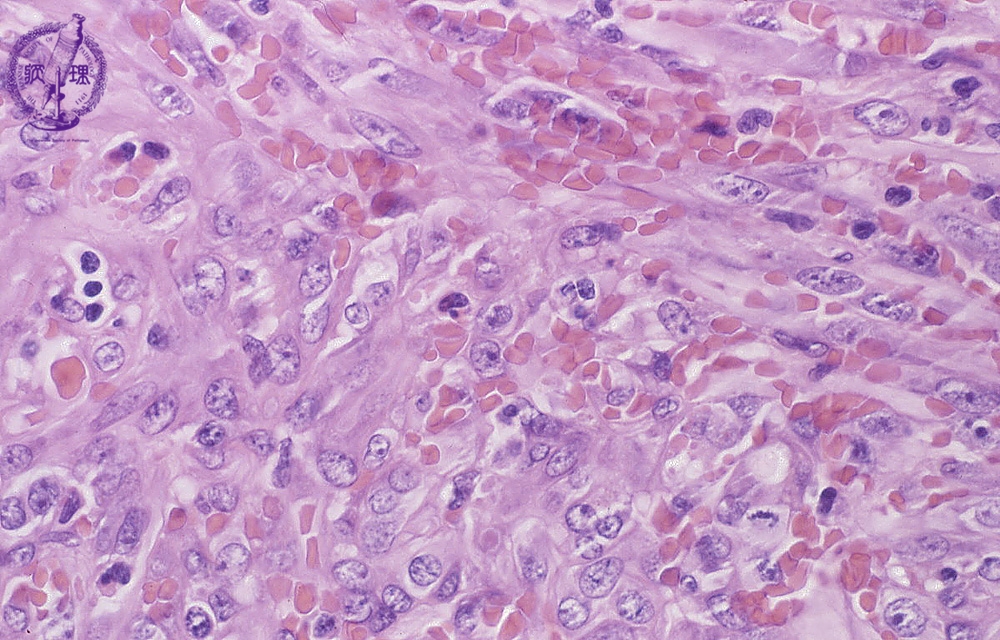

- 18.Soft tissue

- (9)Kaposi sarcoma

Microscopic findings (H.E. high power view): Spindle tumor cells detected in irregular vascular channels surrounded by swollen atypical endothelial cells, like angiosarcoma. Mitotic figures (circle) are frequently detected.

Click the image to see the enlarged image.